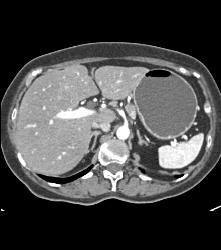

Diagnosis

Antral Carcinoma